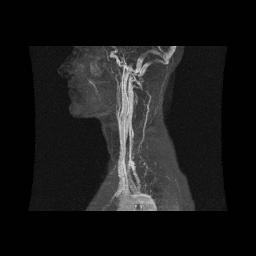

MRI, MRA, and MRV. A two- and three-dimensional image reconstruction, with applications including evaluation and diagnosis of thoracic outlet syndrome (TOS).